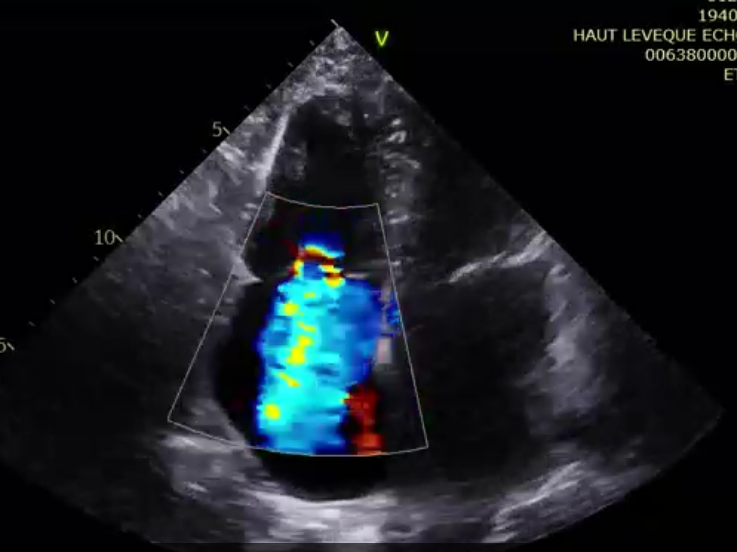

術(shù)后超聲提示微量瓣周漏